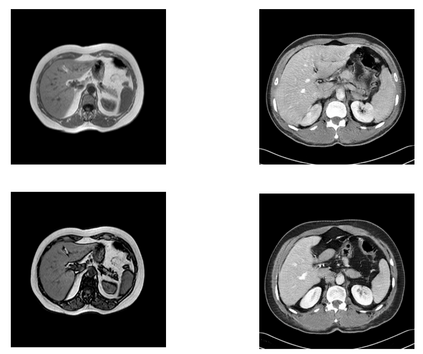

In many clinical settings, the use of both Computed Tomography (CT) and Magnetic Resonance (MRI) is necessary to pursue a thorough understanding of the patient's anatomy and to plan a suitable therapeutical strategy; this is often the case in MRI-based radiotherapy, where CT is always necessary to prepare the dose delivery, as it provides the essential information about the radiation absorption properties of the tissues. Sometimes, MRI is preferred to contour the target volumes. However, this approach is often not the most efficient, as it is more expensive, time-consuming and, most importantly, stressful for the patients. To overcome this issue, in this work, we analyse the capabilities of different configurations of Deep Learning models to generate synthetic CT scans from MRI, leveraging the power of Generative Adversarial Networks (GANs) and, in particular, the CycleGAN architecture, capable of working in an unsupervised manner and without paired images, which were not available. Several CycleGAN models were trained unsupervised to generate CT scans from different MRI modalities with and without contrast agents. To overcome the problem of not having a ground truth, distribution-based metrics were used to assess the model's performance quantitatively, together with a qualitative evaluation where physicians were asked to differentiate between real and synthetic images to understand how realistic the generated images were. The results show how, depending on the input modalities, the models can have very different performances; however, models with the best quantitative results, according to the distribution-based metrics used, can generate very difficult images to distinguish from the real ones, even for physicians, demonstrating the approach's potential.